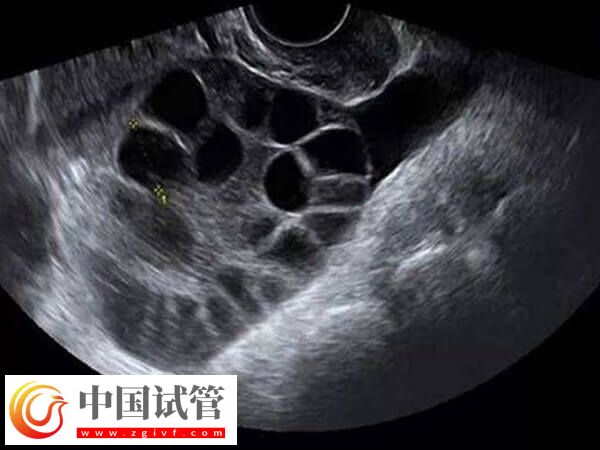

对于试管婴儿治疗,卵泡的大小非常重要,应该在18-30毫米之间。只有在卵泡大小合适的情况下,才可以确保取卵操作进行得顺利,从而获得最佳受精结果。而对于取了16mm卵泡能否进行体外培养,关键得看卵泡的成熟情况。

对于试管婴儿,卵泡的大小是至关重要的。所以IVF治疗过程中还需要诊断师密切关注卵泡的大小,以及卵子的发育状态,以确保收集的卵子质量达到最佳状态。

- 根据医学研究,卵子的大小应该在18-30毫米之间,如果小于18毫米,可以通过激素治疗进行促进,以达到最佳受精条件;

- 如果卵泡大于30毫米,则可能会导致受精率降低,因此在IVF治疗中,卵泡的大小应适中。